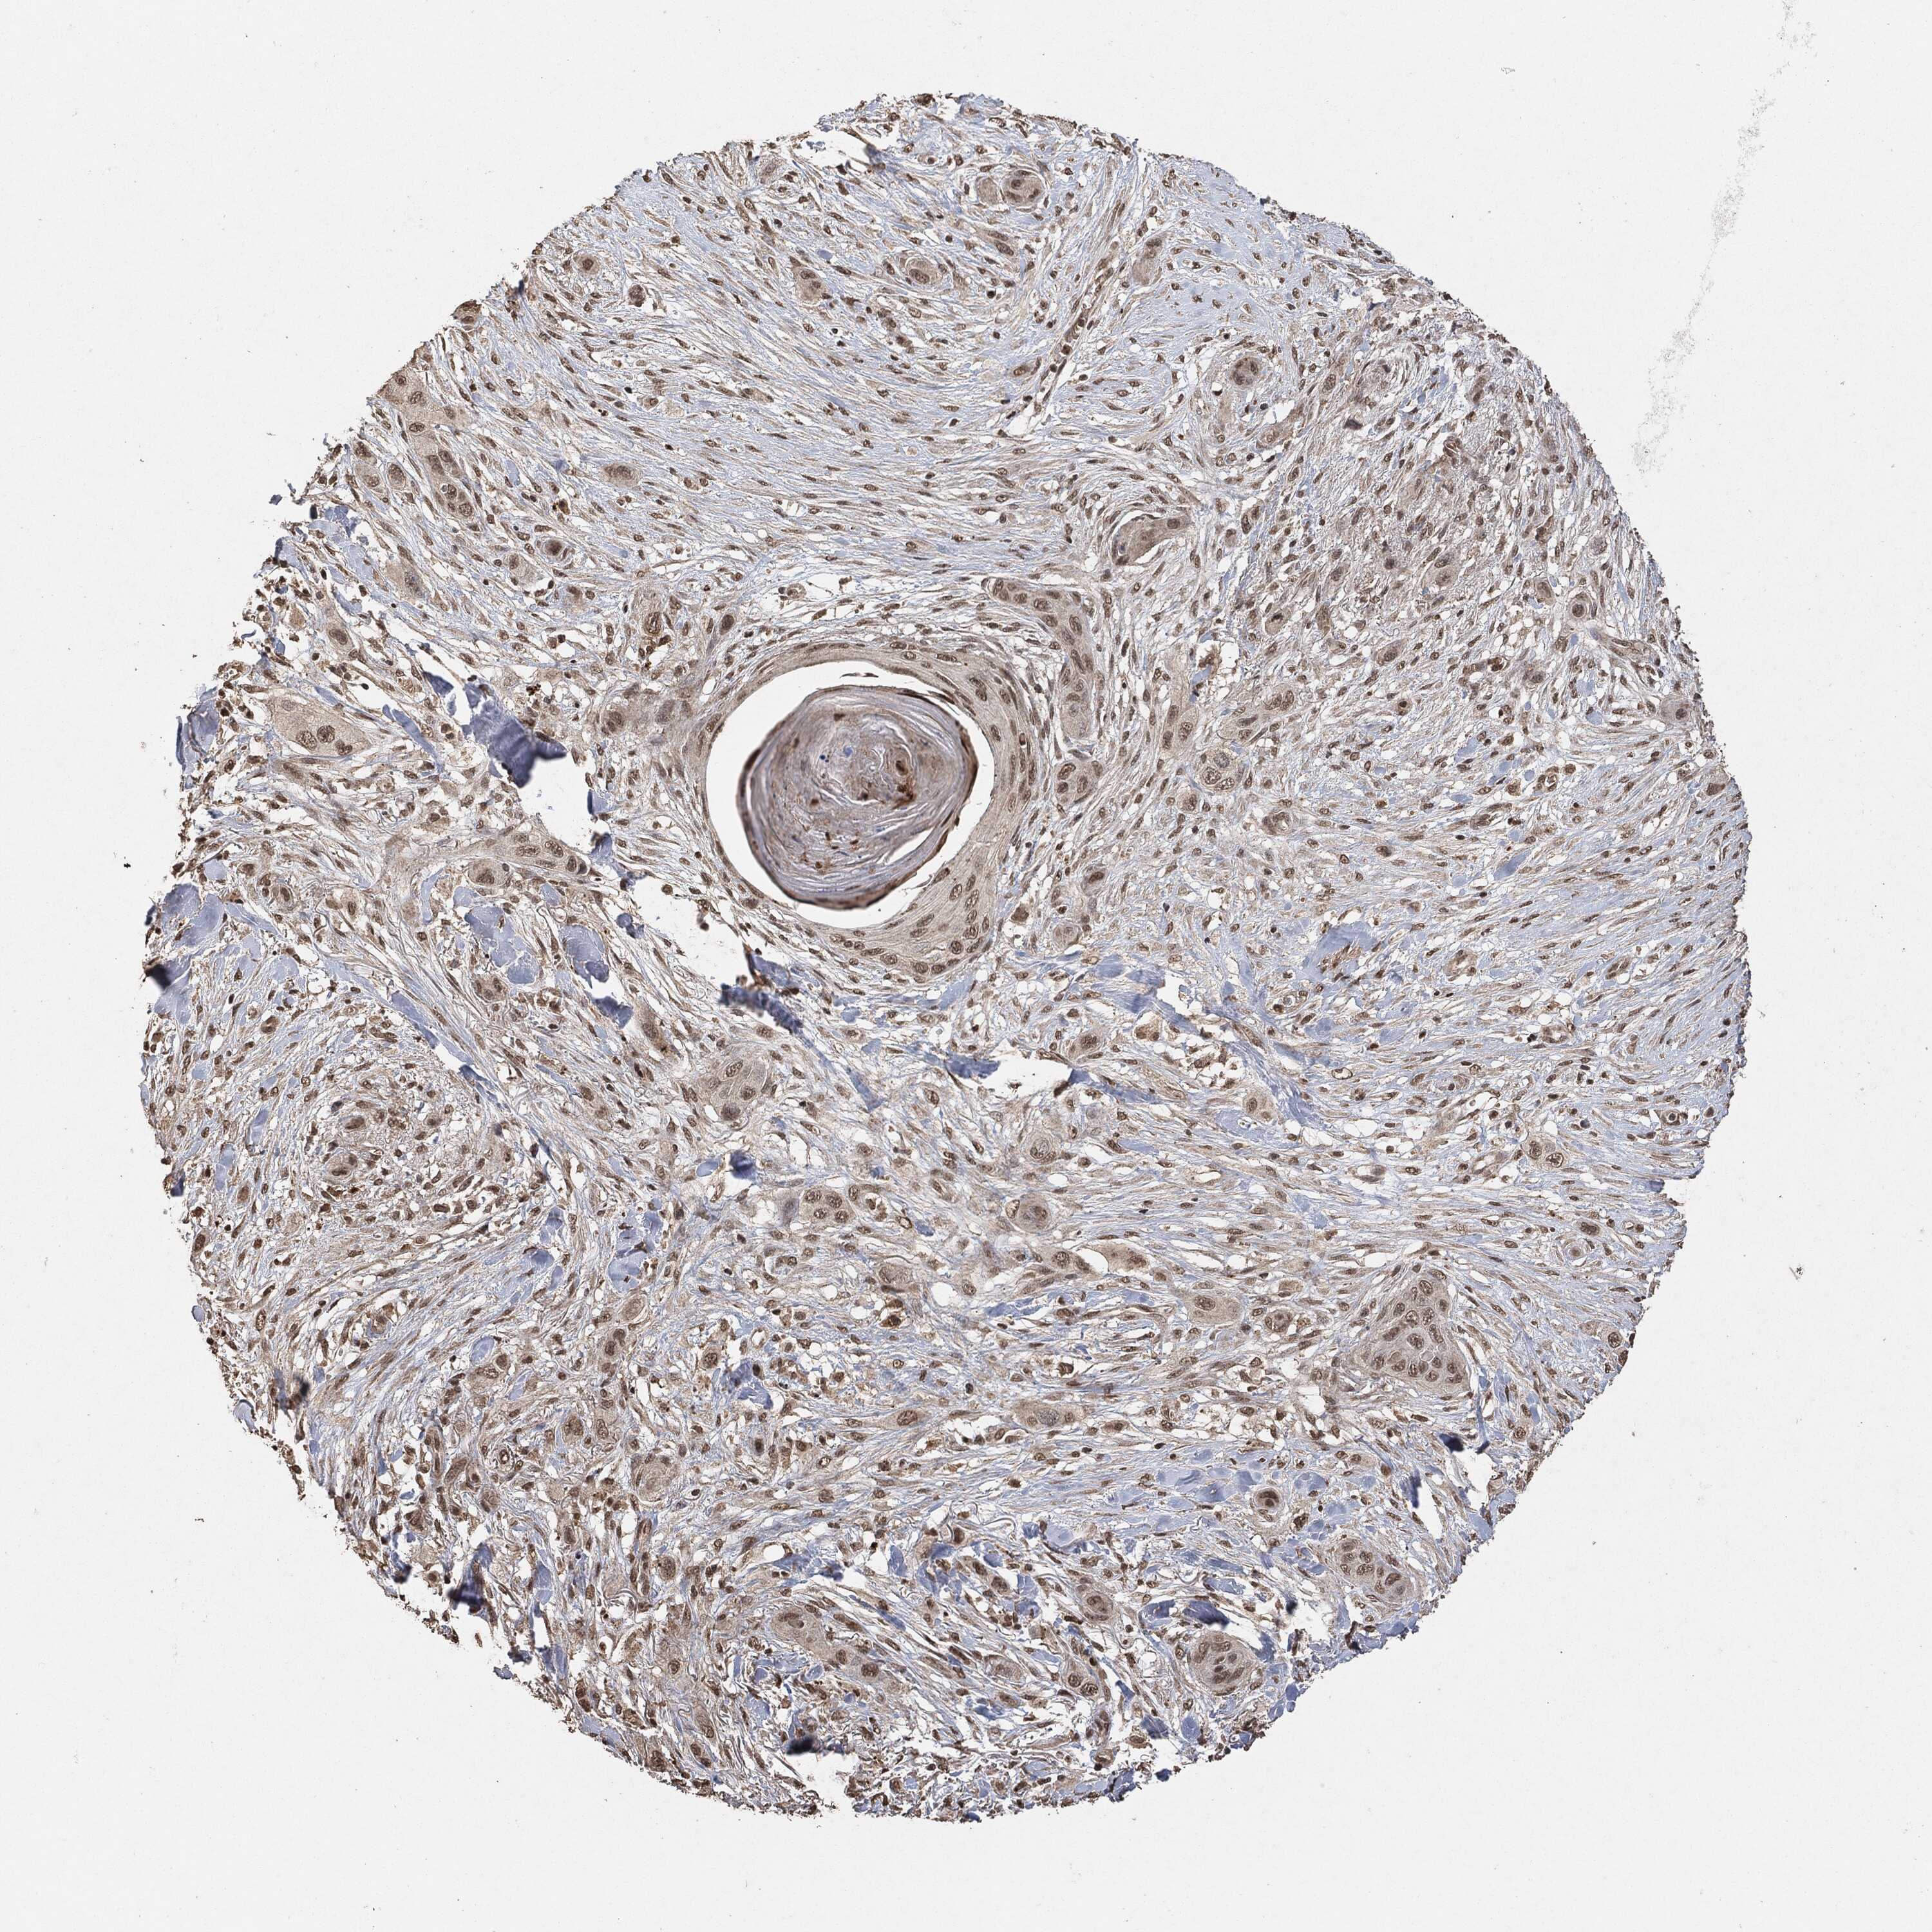

SKIN CANCER - Protein expressioni

A mouse-over function shows sample information and annotation data. Click on an image to view it in a full screen mode. Samples can be filtered based on level of antibody staining by selecting one or several of the following categories: high, medium, low and not detected. The assay and annotation is described here.

Antibody stainingi

Antibody staining in the annotated cell types in the current human tissue is reported as not detected, low, medium, or high, based on conventional immunohistochemistry profiling in selected tissues. This score is based on the combination of the staining intensity and fraction of stained cells.

Each image is clickable and will lead to virtual microscopy that enables deeper exploration of all samples and also displays staining intensity scores, fraction scores and subcellular localization as well as patient and tissue information for each sample.

Basal cell carcinoma